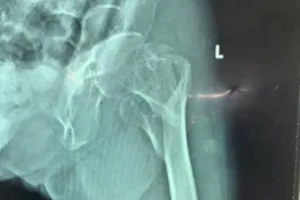

Nối các mảnh xương gãy cho cụ bà 101 tuổi